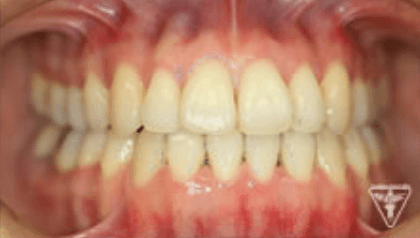

治療後

治療前後の比較